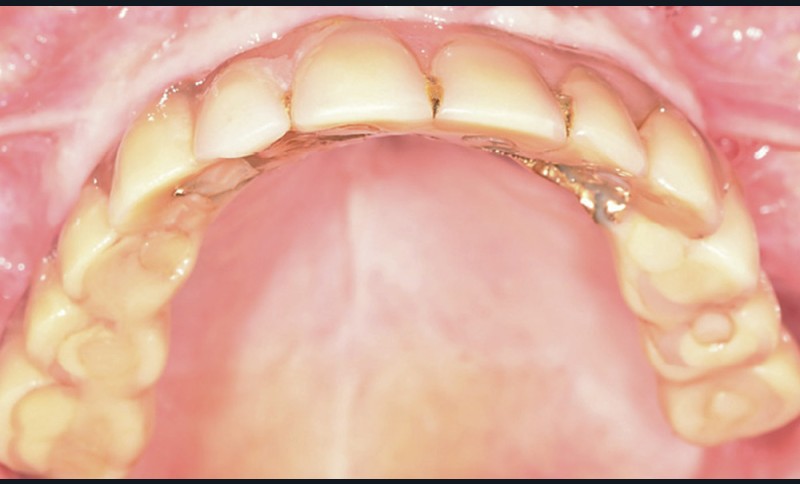

L’examen clinique exo-buccal de face montre une légère dysharmonie des étages moyens et inférieurs de la face et une altération de la dimension verticale (fig. 1). L’examen clinique exo-buccal de profil met en évidence une classe III squelettique dans un contexte d’hypo-divergence [1, 2]. L’examen clinique endo-buccal révèle l’existence d’une réhabilitation totale fixée supra-implantaire au maxillaire nécessitant des manœuvres de maintenance et un édentement mandibulaire subtotal de classe I.1 [3, 4] conservant les dents 33 et 43 (fig. 2). La crête osseuse mandibulaire résiduelle présente une résorption osseuse limitée en hauteur et en largeur, correspondant à une classe topographique 3 [5, 6].